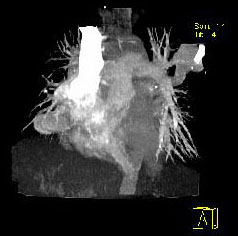

男性,26岁,头晕、气逼三年余,CT检查如图所示,请选择的最可能诊断 ( ) XN-27051.jpg XN-27052.jpg XN-27053.jpg XN-27054.jpg

题型: 单选题 分类: 心血管内科

• D.动静脉畸形